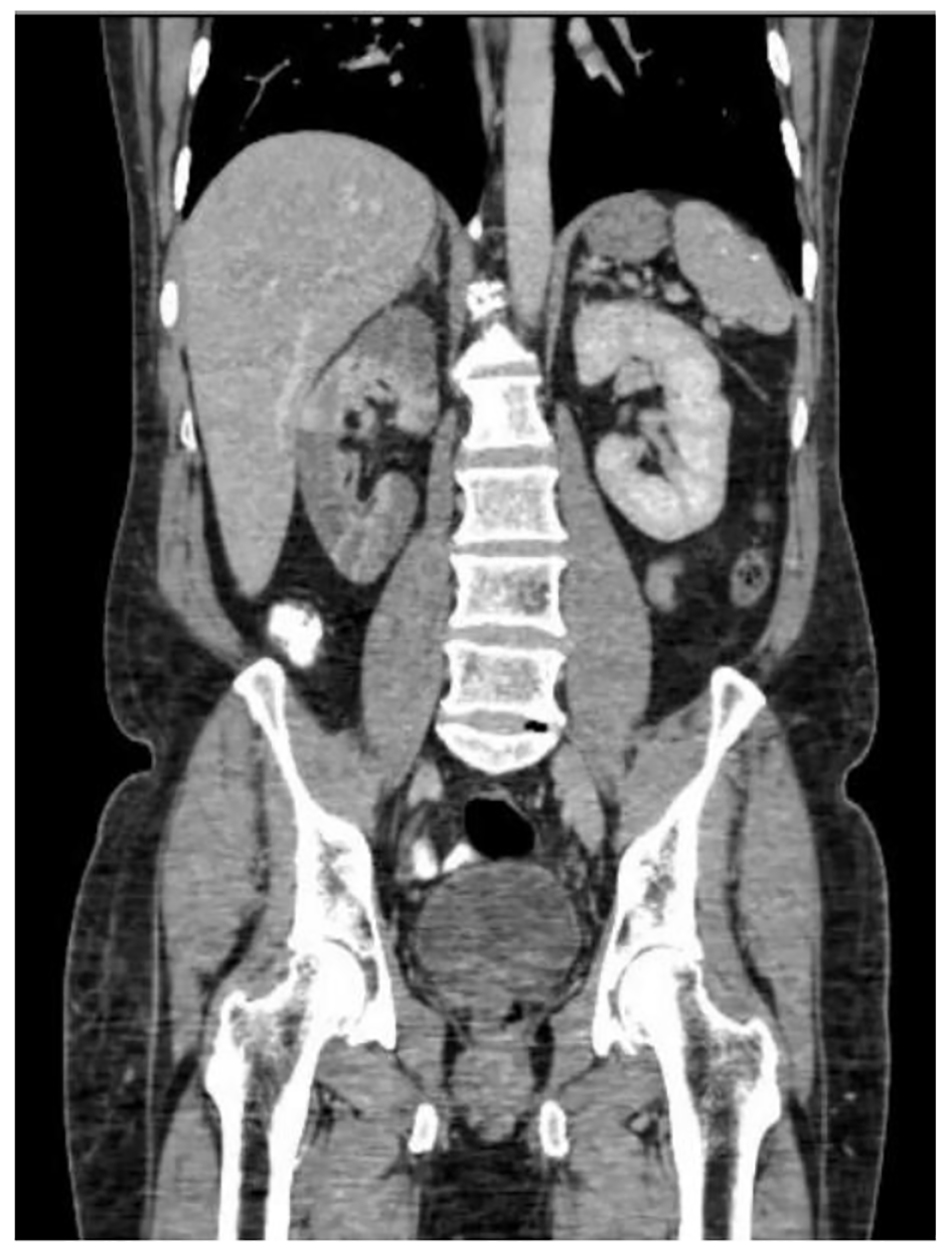

A 56-year-old man with medical history of hypertension and diabetes mellitus presented to emergency department with complaint of sudden onset of severe right lower abdominal pain for 1 day. History was negative for urinary symptoms, constipation or diarrhea, trauma to abdomen or alcohol abuse. Three weeks prior, he was admitted in intensive care unit for suicidal attempt with acetaminophen overdose. History was negative for fever, chills, joint pain, rashes or kidney stones. Vital signs in emergency department showed BP 145/74, HR 87/min, RR 16/min, and temperature 36.3 °C. Systemic examination was positive for mild tenderness at right lower abdomen and severe tenderness at right costovertebral angle. Chest exam was normal, cardiovascular exam revealed systolic murmur at the mitral area and patient said he was told to have murmur in the past. Initial lab tests revealed WBC 16,650, Hb 14.4 g/dL, and platelet 432,000. Urinalysis showed WBC 6 - 10, RBC 3 - 5, negative leukocyte esterase and nitrite. Liver function showed ALT 77, AST 116, LD 1,051 with normal bilirubin, albumin and INR. Liver function was probably deranged from recovering liver injury from acetaminophen overdose but LD was disproportionately high. Urine drug screen was negative. CT scan of abdomen with contrast showed striated appearance of the right kidney with hypoperfusion and wedge-shaped hypodensities throughout the kidney (Figs. 1 and 2). Given radiographic appearance, acute onset, and evidence of leukocytosis, pyelonephritis versus multifocal infarction were suspected. He was started on antibiotics for pyelonephritis. But the clinical picture was more favorable for kidney infarction due to absence of fever, urinary symptoms and normal urinalysis. Urine culture showed mixed flora. Ultrasound with Doppler study showed relative decrease in blood flow within the right peripheral renal cortex compared to the left and the study was negative for renal artery stenosis. Lactate dehydrogenase was elevated to 1,051 at admission, peaked at 2,049 and decreased to 733 at the time of discharge. Due to disproportionate rise of lactate dehydrogenase, renal infarct was the more likely cause. Electrocardiogram showed normal sinus rhythm with no evidence of atrial fibrillation. The patient developed fever during hospital stay and blood culture was positive for methicillin sensitive Staphylococcus auricularis. Transthoracic echocardiogram was normal, but due to persistent fever, transesophageal echocardiogram was done that showed no vegetation and showed trivial mitral and tricuspid regurgitation with normal left ventricular ejection fraction.

![]() Click for large image | Figure 1. CT scan of abdomen showing renal infarction. |